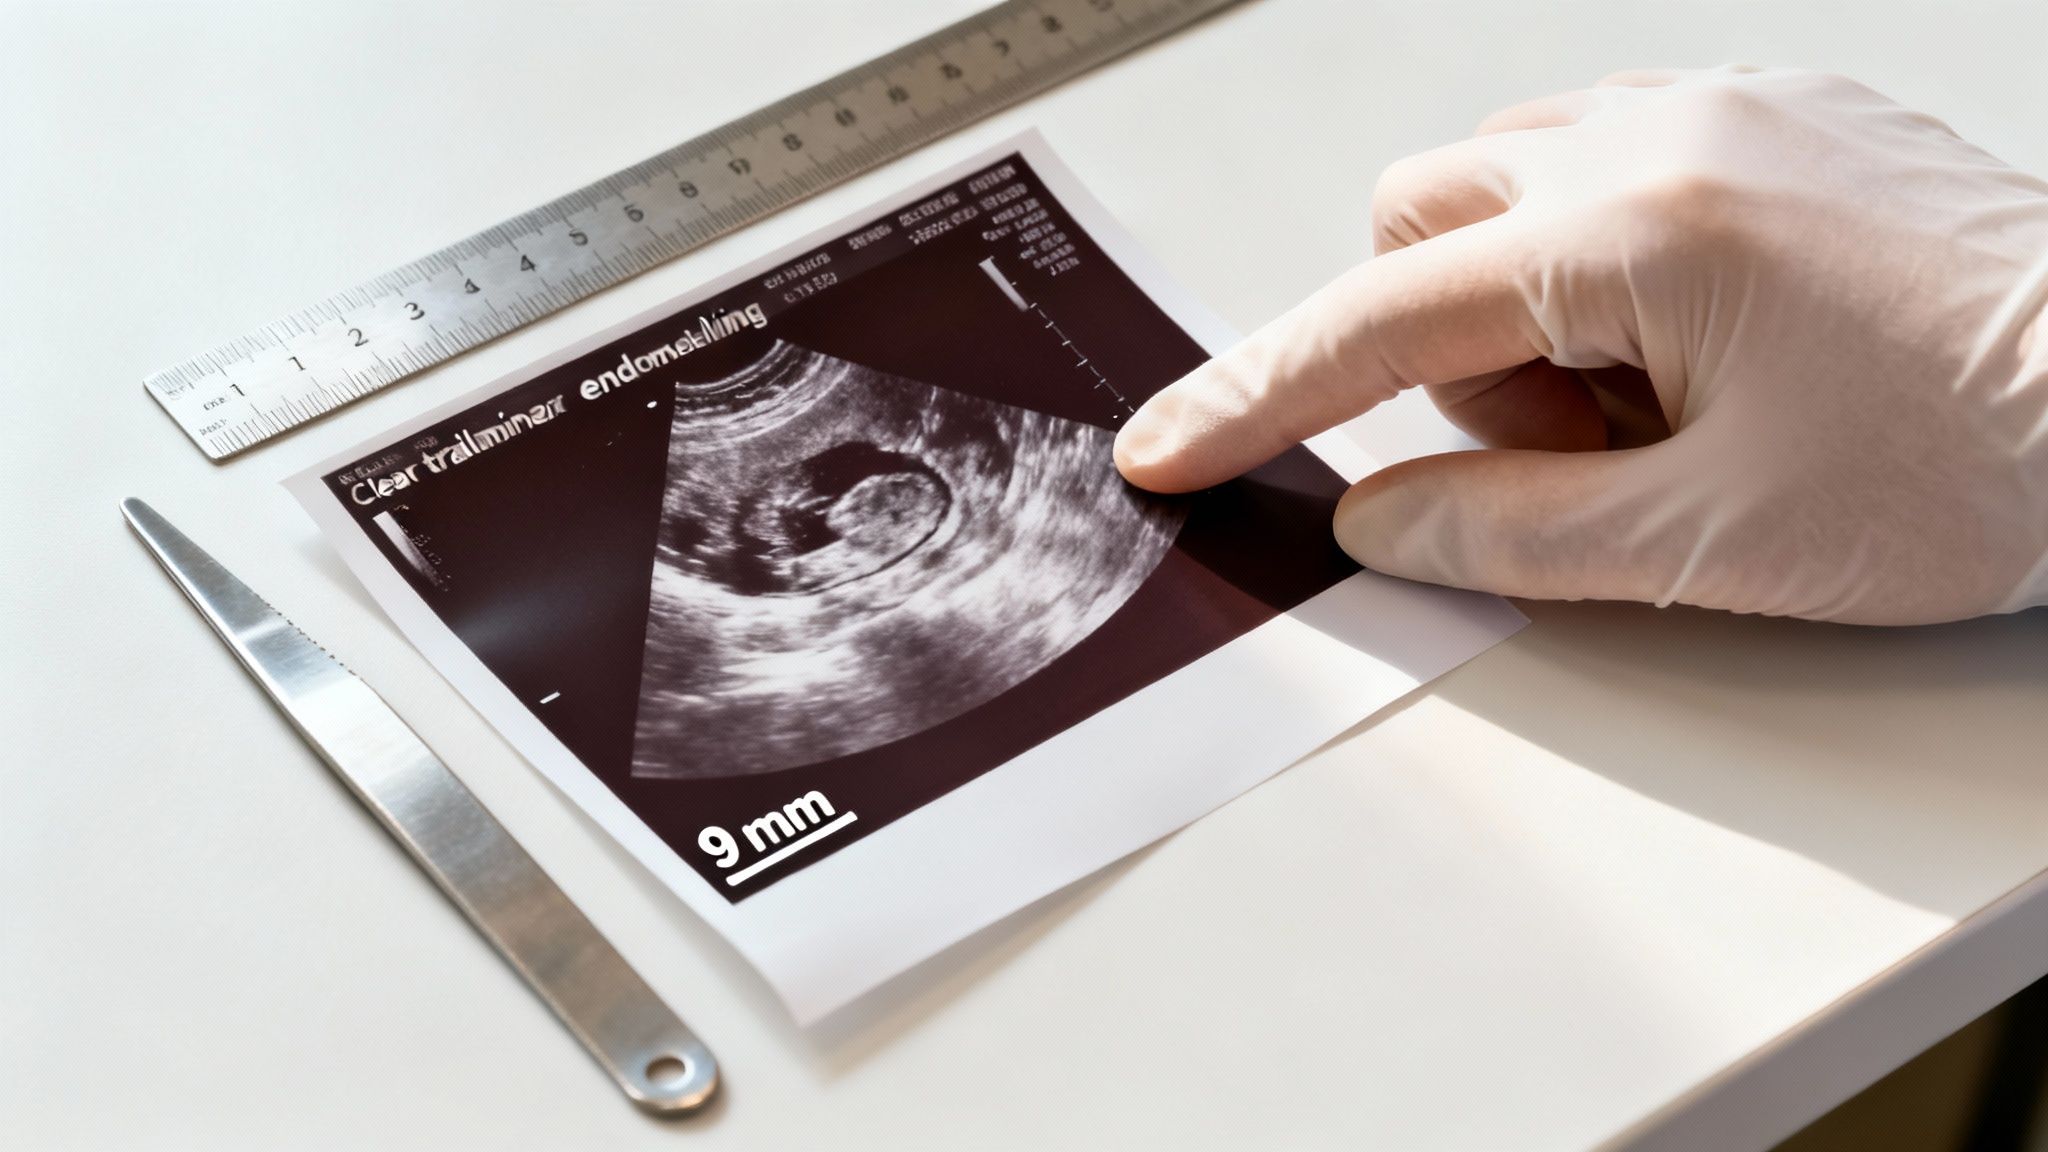

The final scans are all about confirming when this star follicle reaches full maturity. For a follicle, the "finish line" is typically a size between 18 mm and 25 mm. Hitting this size is the signal that it’s ripe and ovulation is just around the corner—usually within the next 24 to 36 hours.

A mature follicle measuring over 18 mm is the clearest indicator in a follicular study that your body is ready to ovulate. It’s the peak moment the entire tracking process has been leading up to.

As you get closer to ovulation, your report will zero in on two key features of the endometrium: its thickness and its pattern. Both give us vital clues about how receptive it is.

For the best shot at successful implantation, fertility specialists generally like to see an endometrial thickness of at least 8 mm around ovulation. While pregnancies can certainly happen with linings that are a bit thinner, this measurement is often seen as the ideal target. A lining over 8 mm suggests a healthy, well-nourished foundation.

You might come across the term "trilaminar pattern" in your report. This is a fantastic sign! It describes a distinct three-layered appearance on the ultrasound, looking like a triple line. This pattern is considered the gold standard indicator that the endometrium is perfectly primed and ready for implantation.